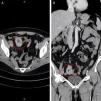

Upon her arrival at the emergency service, the patient was stable, with vital signs within normal parameters. She stated having nonradiating abdominal pain of moderate intensity in the right iliac fossa, nausea, vomiting of gastric content, and hematochezia. She received symptomatic treatment with no clinical improvement. Physical examination revealed an unaltered abdomen. In her laboratory tests, hypochromic microcytic anemia stood out and the rest were within normal parameters. Abdominal computed tomography with intravenous contrast identified bowel occlusion, with intussusception at the level of the terminal ileum and a polyp in its interior (Fig. 1A [axial view] and B [coronal view]). As part of the approach, retrograde single-balloon enteroscopy was performed, revealing an indurated, friable, fibrin-covered exophytic lesion with mucous and vascular pattern loss that involved more than 80% of the lumen (Fig. 2A and B). Biopsies were taken and the adjacent area was marked with India ink. The histopathologic report was received later and was consistent with primary adenocarcinoma of the ileum (Fig. 3A [asterisk], B, and C). Extension studies were performed that documented enhancement only at that level. As part of the treatment, laparoscopy with intestinal resection, guided by the previously marked India ink tattoo, was performed. An extracorporeal mechanical side-to-side anastomosis was carried out, reporting a 2 × 2 cm tumor, with no invasion into adjacent structures, and malignancy-free margins. The patient was evaluated by the oncology service and later discharged with no eventualities. She is currently asymptomatic, and her progression is good. Follow-up will be carried out at the oncology service.